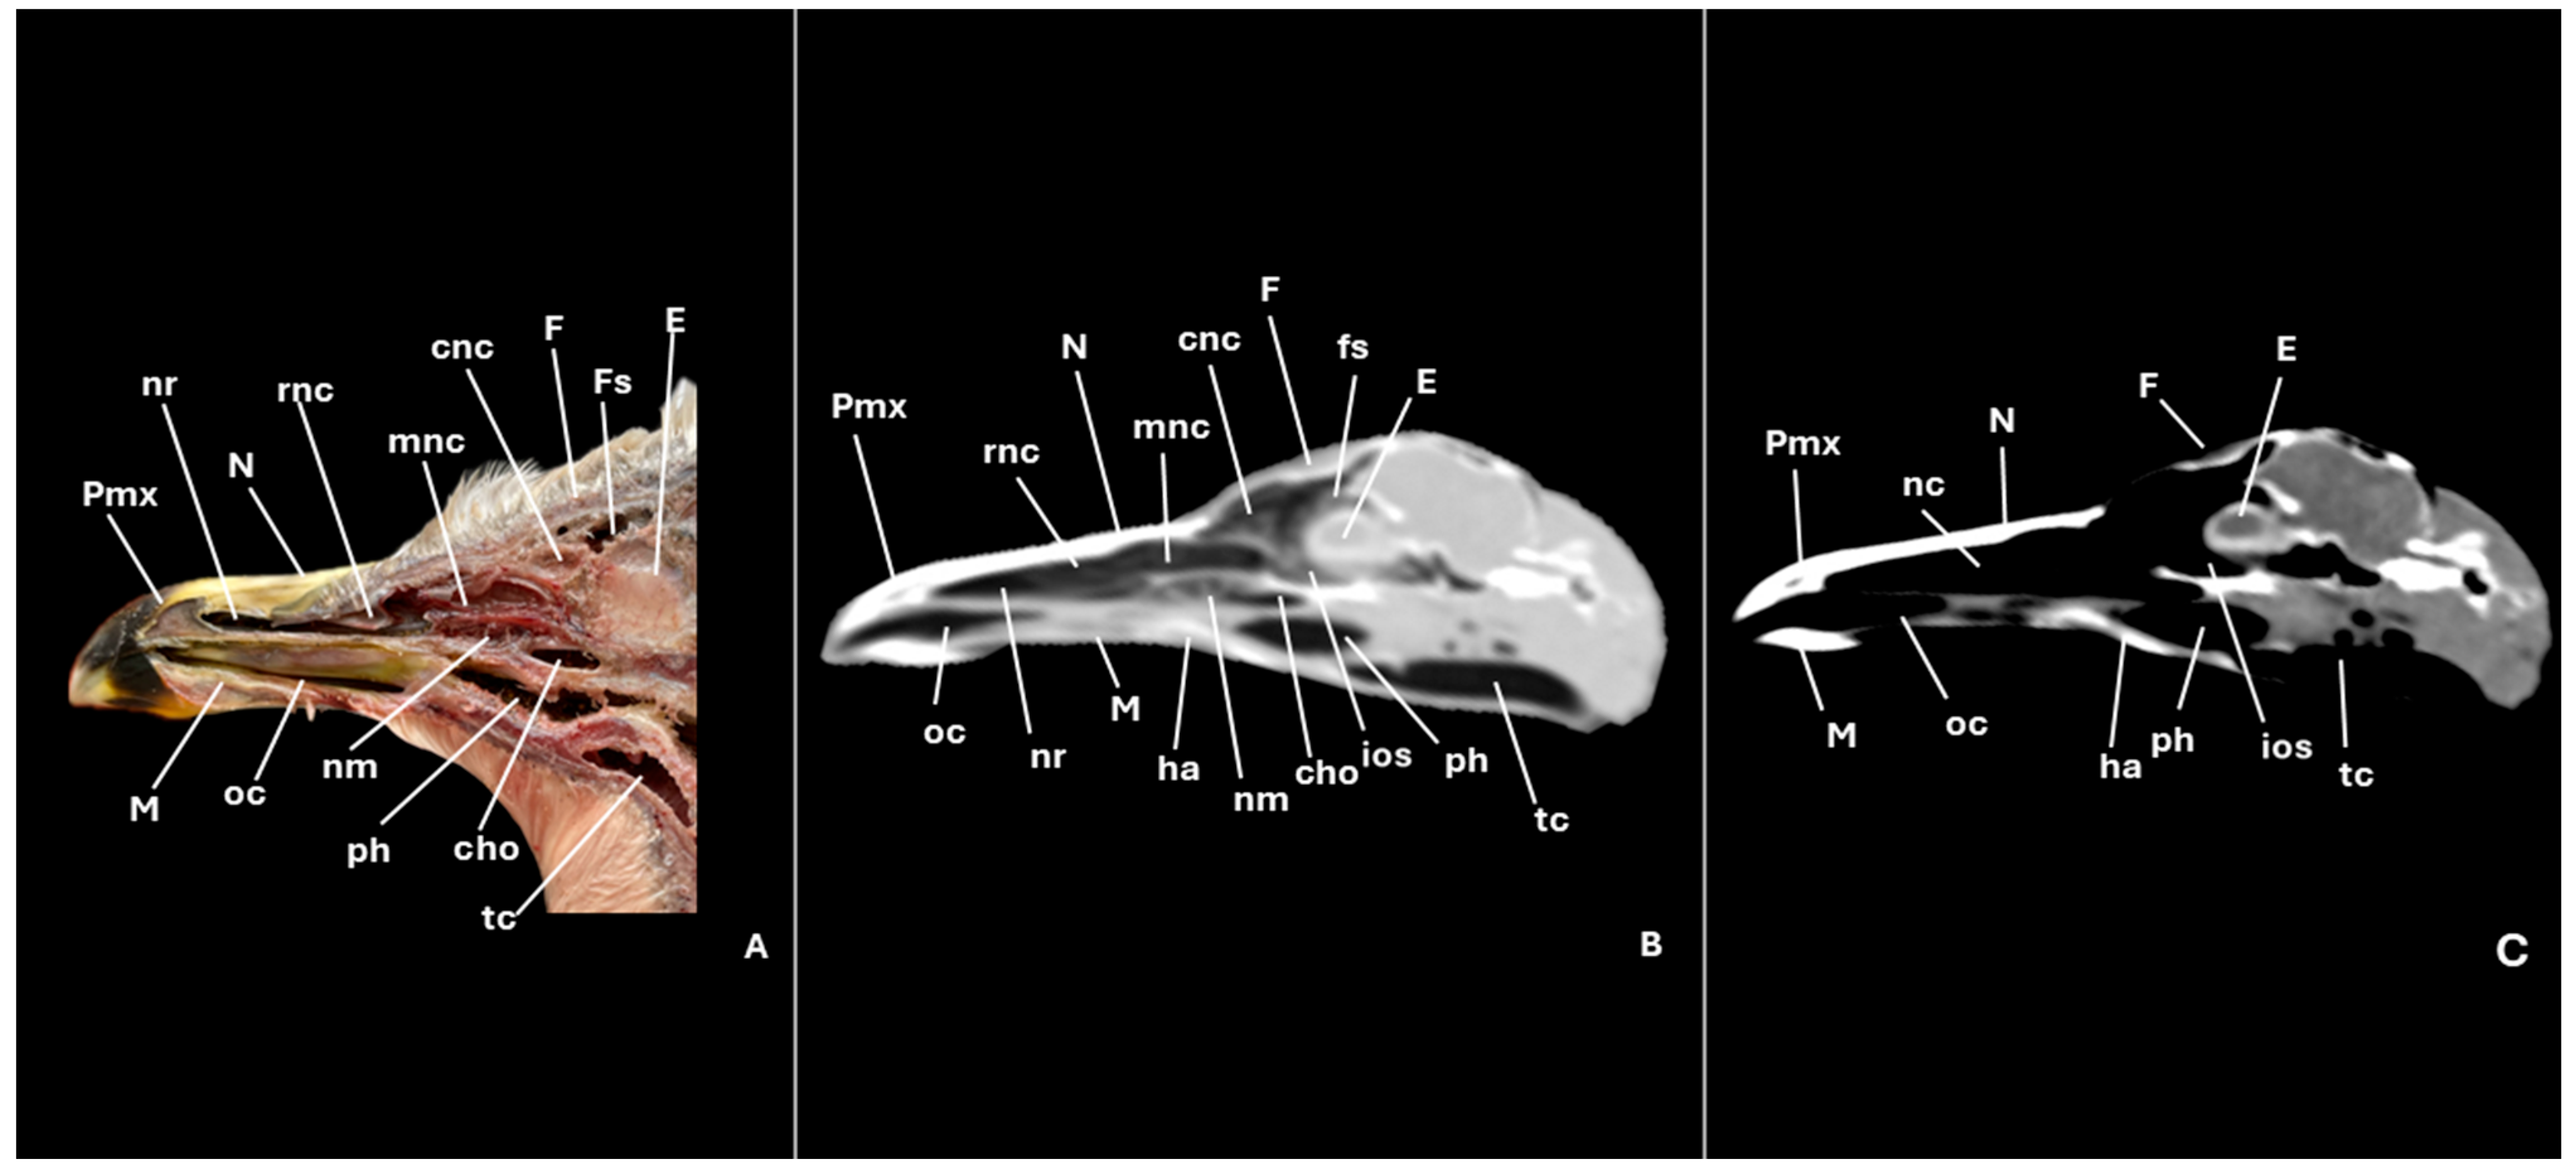

3.1. Anatomical Cross-Sections

3.2. Computed Tomography (CT)